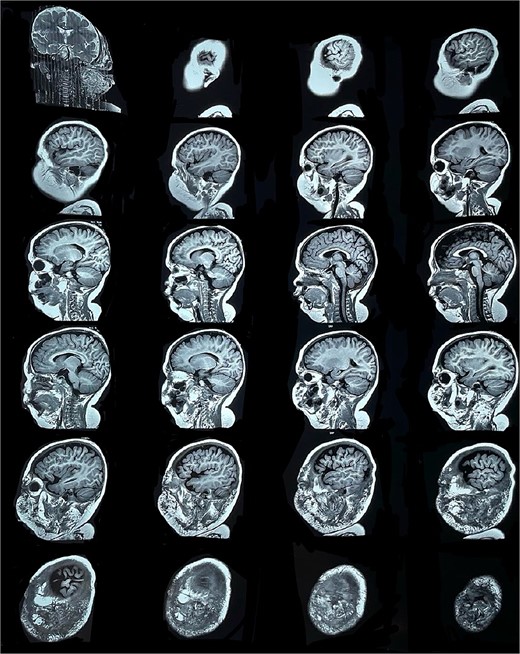

Six months later, the patient developed fever and severe edema that prevented the opening of the left eye, resulting in decreased overall tolerance. Laboratory results showed leukocytosis, severe thrombocytopenia (platelet count of 6000), and a positive C-reactive protein test. Physical examination revealed an irritable and lethargic patient with a 15 × 20 cm red mass with irregular borders (Fig. 1). An angioresonance was performed, revealing a hemangioma on the left hemiface that infiltrates muscle planes, the left parotid gland, and the auricular pavilion, ~10.7 × 6.6 × 13 cm in size, with possible vascularization from branches of the external carotid artery (Figs 2 and 3), leading to the diagnosis of KMP.

Angioresonance with evidence of a hemangioma on left hemiphase (coronal plane).